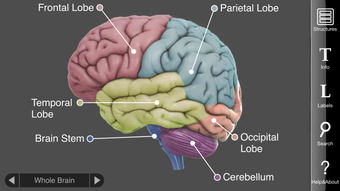

3D Cerveau : Explorez les subtilités du cerveau humain.

3D Brain est un programme éducatif et de référence développé par le Cold Spring Harbor Laboratory. Disponible sur la plateforme iPhone, cette application gratuite permet aux utilisateurs d'explorer et d'apprendre les structures complexes du cerveau humain.

En utilisant l'écran tactile, les utilisateurs peuvent faire pivoter et zoomer sur 29 structures cérébrales interactives. Chaque structure fournit des informations détaillées sur ses fonctions, ses troubles, les lésions cérébrales, des études de cas et des liens vers des recherches modernes. Ces informations complètes aident les utilisateurs à comprendre comment chaque région du cerveau fonctionne, ce qui se passe lorsqu'elle est blessée et comment elle est impliquée dans les maladies mentales.

Créé par Vivid Apps et le studio d'animation biomédicale AXS pour le DNA Learning Center du Cold Spring Harbor Laboratory, 3D Brain est un outil inestimable pour toute personne intéressée par les neurosciences ou l'étude du cerveau humain. Que vous soyez étudiant, chercheur ou simplement curieux du cerveau, cette application offre une expérience captivante et informative.